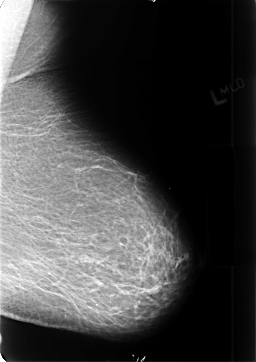

B_3402_1.LEFT_MLO

LEFT_MLO LINES 4704 PIXELS_PER_LINE 3320 BITS_PER_PIXEL 12 RESOLUTION 50 NON_OVERLAY